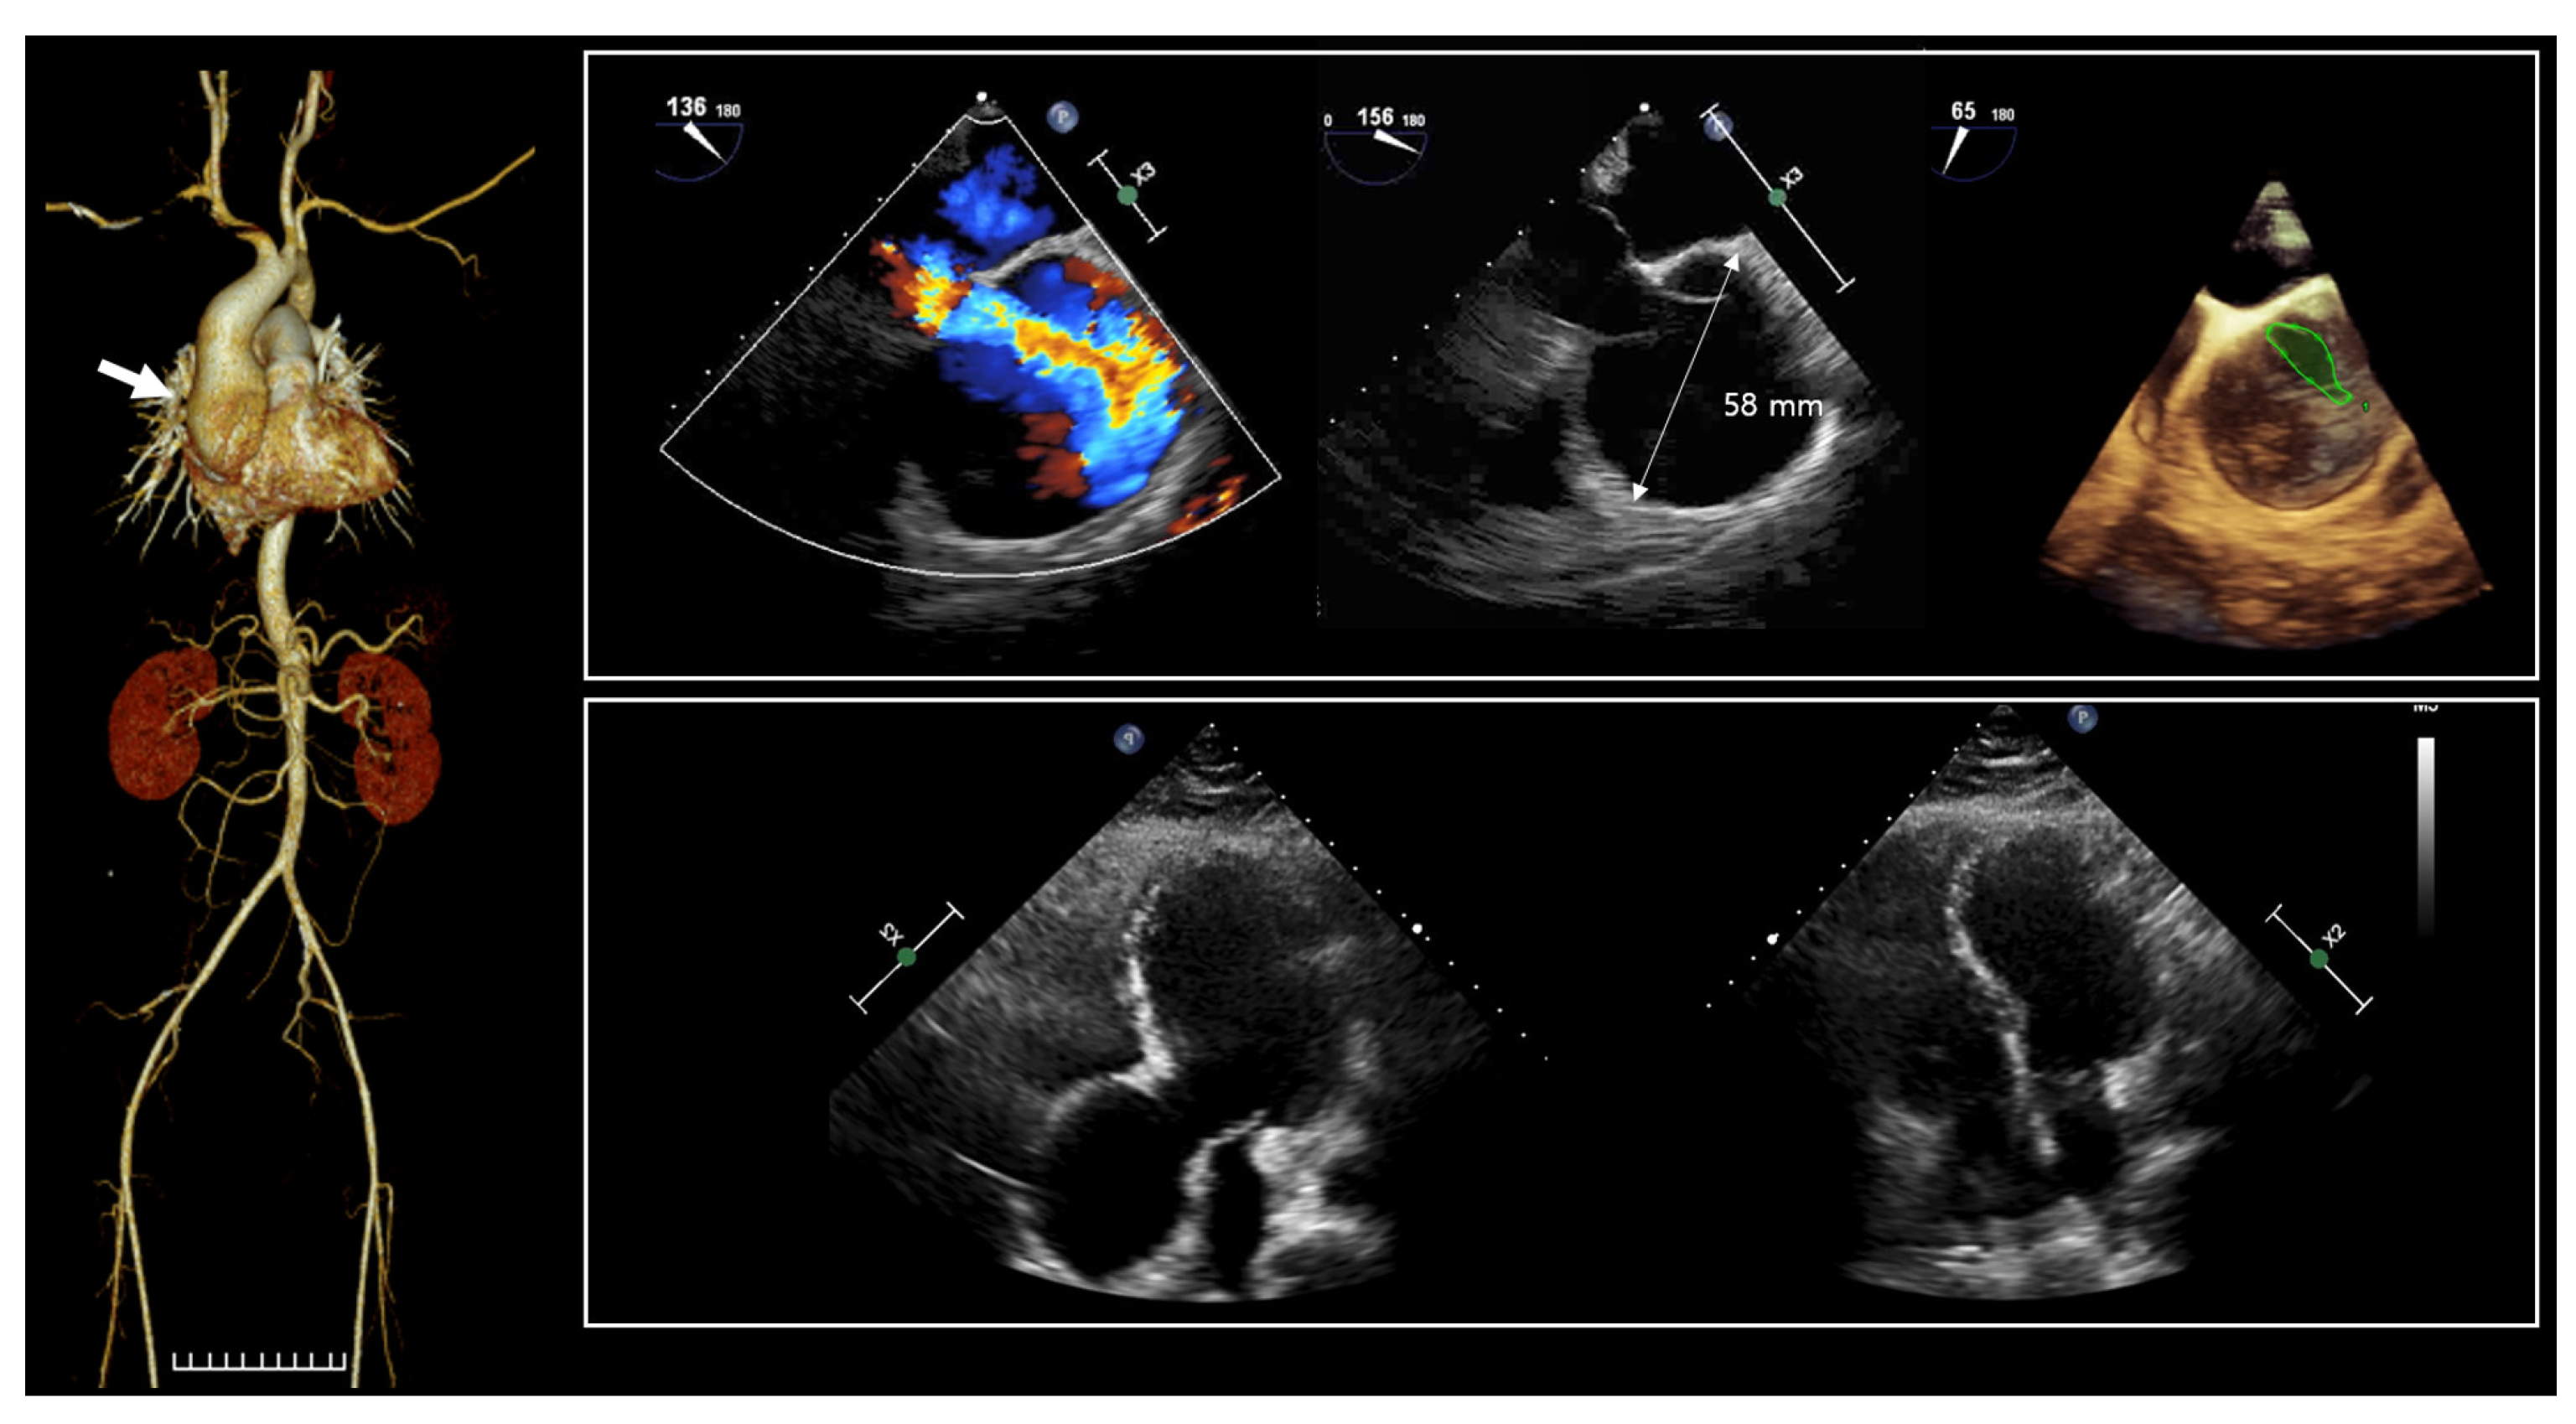

The proband (II-1 in Figure 1a), a 36-year-old man, was admitted to the hospital due to dyspnea. Since birth, he has experienced hypotonia, blindness in both eyes, and hearing impairment. He was the first child of nonconsanguineous parents, and the pregnancy was uneventful at 38 weeks of gestation. Family history was unremarkable. His growth percentiles were within normal ranges at birth. In the early infant period, he showed generalized hypotonia, and growth motor slowly improved in childhood. Throughout his early development, he displayed global developmental delay, eventually reaching borderline intellectual disability (ID) with an intellectual quotient of 75 using the Wechsler Adult Intelligence Scale. As a result, he attended a specialized school for handicapped children due to total blindness and a borderline IQ. He did not live independently and required assistance for daily living. Moreover, he encountered challenges in obtaining employment. Snoring has been a consistent issue since childhood, leading to a diagnosis of obstructive sleep apnea based on polysomnogram results. His body mass index was 28 kg/m2 (90th percentile), which corresponds to overweight. Upon admission, vital signs were stable, with blood pressure at 110/60 mmHg, heart rate at 60 beats per minute, respiratory rate at 16 beats per minute, and body temperature at 36.6 °C. Physical examination revealed several abnormalities, including short stature (153.7 cm, below the 3rd percentile), a short neck, pectus carinatum, humped back, excess nuchal skin, facial dysmorphism (swollen eyelids, blepharophimosis, wide nasal bridge, a high forehead), vertebral anomaly, arachnodactyly, and edema in both lower extremities (Figure 1b). He was diagnosed with almost total blindness with nonlight perception at around 2 years old, and an ophthalmologic examination revealed optic atrophy (Figure 1c). Brain magnetic resonance imaging indicated diffuse cerebral atrophy, and cervical computed tomography scan revealed disc bulging with spondylosis (Figure 1d). Laboratory findings showed an elevated N-terminal prohormone of brain natriuretic peptide (248.10 pg/mL; reference range, 42.5 to 106.4), while highly sensitive troponin T (0.004 ng/mL; reference range, <0.014) and creatine kinase-MB (0.90 ng/mL; reference range, <2.2) were within normal limits. Nonspecific findings were observed in complete blood count, blood chemistry, metabolic screening, and urinalysis. Two years prior to admission, a transthoracic echocardiogram (TTE) conducted at the outpatient setting displayed normal left ventricular systolic function with an ejection fraction (EF) of 59%, and the ascending aorta measured 45 mm in diameter. Due to poor echo windows caused by pectus carinatum, assessment of the aortic valve and aortic root was inconclusive. A chest aorta computer tomography scan (CT) performed during the present admission revealed marked aneurysmal dilatation, approximately 5.8 cm from the aortic annulus to the proximal ascending aorta (Figure 2). A three-dimensional transesophageal echocardiogram exhibited aortic root aneurysm and bicuspid aortic valve (sinus of Valsalva = 58 mm) (upper panel in Figure 2). TTE during the current admission showed dilatation of the aortic root and right ventricular dilatation (lower panel in Figure 2).

The patient’s aortic root aneurysm increased from 45 mm to 58 mm in two years, and a TRAF7 gene mutation was identified, leading to a Bentall operation. Postoperative imaging findings (Figure 3a–d) revealed improvement in dyspnea symptoms, although desaturation events persisted during sleep. Facial CT (Figure 3e) and laryngoscopy (Figure 3f) revealed narrowing extending from the nasopharynx to the oropharynx.

Figure 2. Computed tomography scan of the chest aorta revealed aneurysmal dilatation of about 5.8 cm from the aortic annulus to the proximal ascending aorta (arrow). Color doppler echocardiography of aortic root aneurysm; red and blue represents flow towards and away from the transducer, respectively. A 3-dimensional transesophageal echocardiogram shows aortic root aneurysm and bicuspid AV (sinus of Valsalva = 58 mm) (upper panel). Bicuspid AV is represented by green outline. Transthoracic echocardiography at present admission showed dilatation of aortic root and RV dilatation (lower panel).